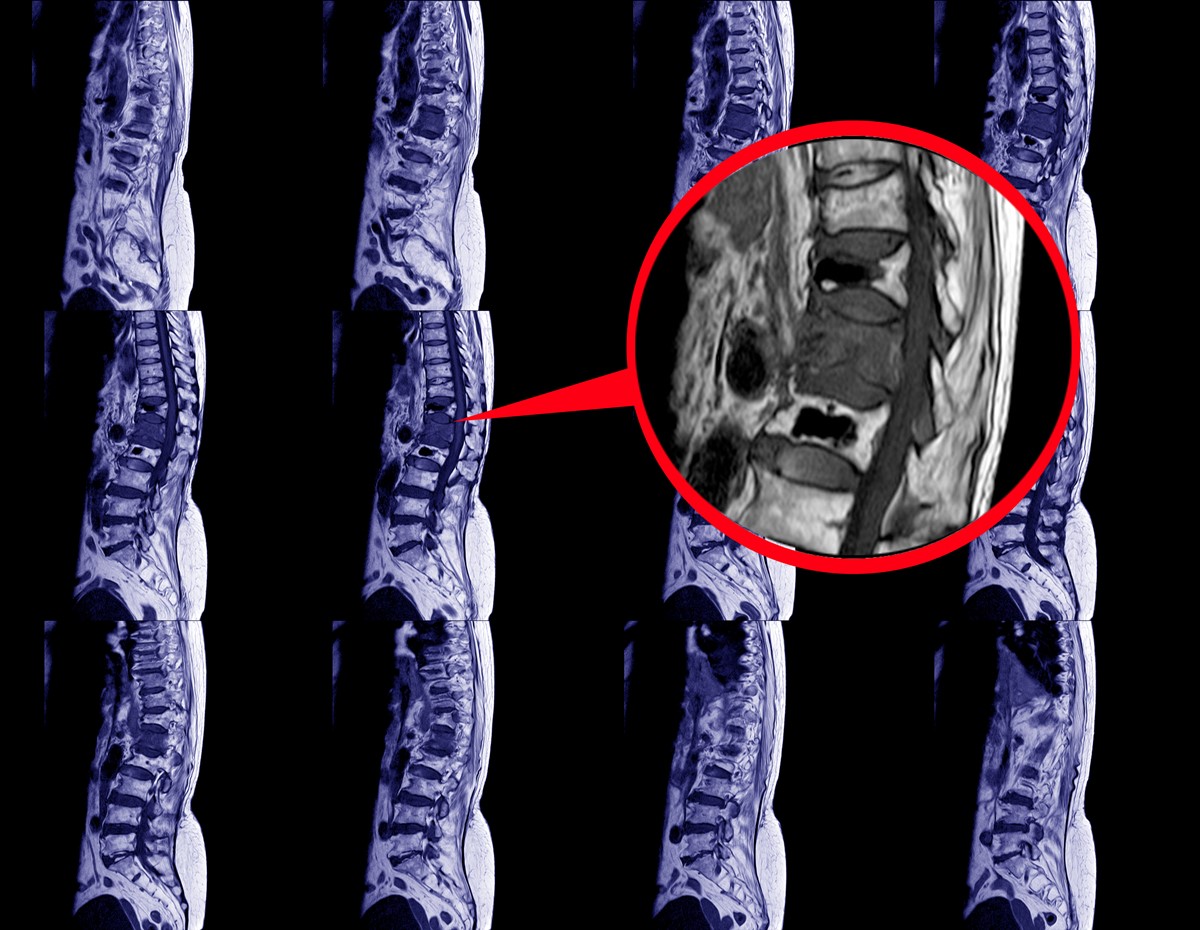

An MRI scan of the brain and spine is done to look for possible radiological evidence of the disease such as atrophy of the cerebellum. A spinal tap can also be done to look for possible evidence.